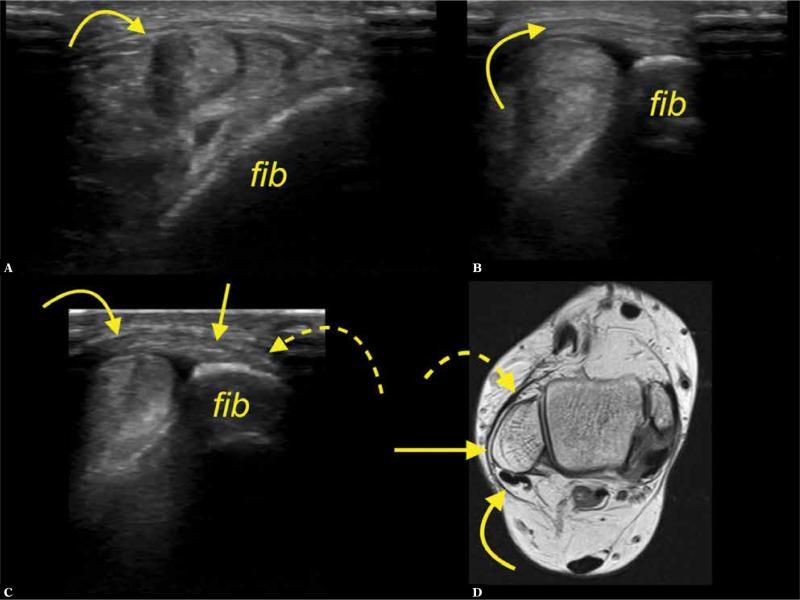

Fig. 4.

A 42-year-old patient presenting clinical suspicion of synovitis. A, B, C. transverse section on ultrasound, d-proton density-weighted oblique oriented section. The interconnection (arrows) between the SPR (curved arrow) and IER (dashed arrow); fib-fibula

The IER served as an intermediate station for connecting the SPR to the ATFL in 8 cases on MRI (12.7%) and in 5 cases on US (7.9%), but the difference was not significant (p >0.05) (Fig. 3). In those cases, a direct connection between the SPR and the ATFL was also noted (n = 13, 20.6%) (Fig. 5).